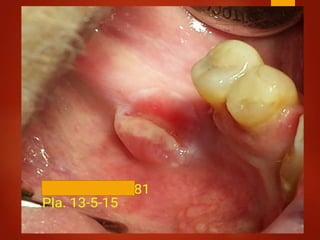

El documento es un registro médico odontológico que muestra las fechas de las visitas de un paciente al centro de salud El Raval, incluyendo exámenes y tratamientos realizados como la extracción de cálculos salivales en abril y mayo de 2012.